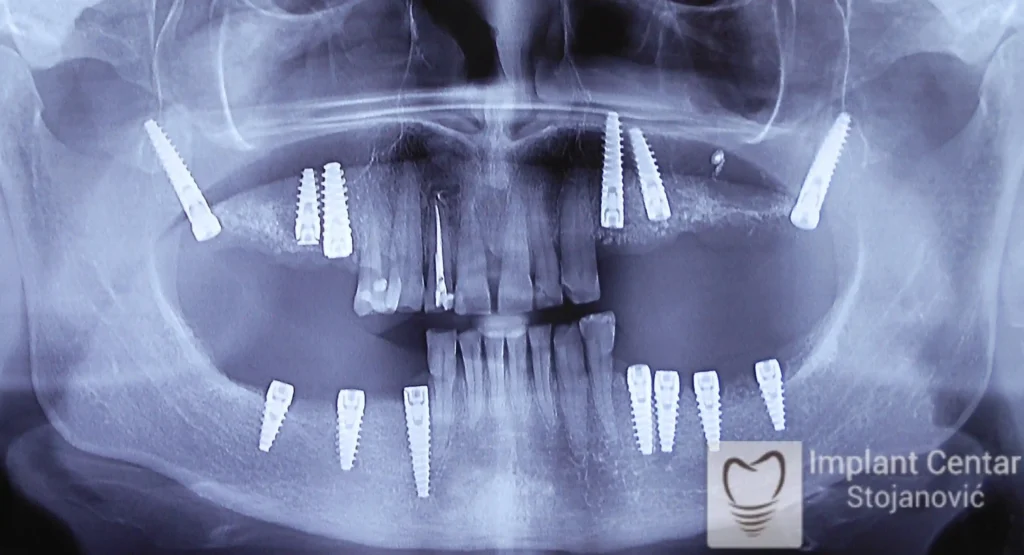

Na slici 1. slici 2. vidi se početno stanje — pacijent je imao prirodne zube, ali samo izradom novih mostova nije bilo moguće postići normalan odnos gornjih i donjih zuba (eugnatan zagrižaj).

Zbog toga je plan terapije uključivao vađenje svih preostalih zuba i ugradnju implantata u gornjoj i donjoj vilici. U gornjoj vilici postavljena su i dva tuberopterigoidna implantata, kao zamena za sinus lift proceduru, što se može videti na ortopan snimku nurađenom odmah nakon ugradnje (slika 3).

Već tri dana nakon operacije, pacijent je zbrinut fiksnim privremenim zubima na implantatima, čime je odmah povraćena funkcija i estetika osmeha.

Nakon završetka perioda integracije implantata, izrađeni su cirkonijum-keramički mostovi u gornjoj i donjoj vilici (slika 6.).

Pacijent ističe da je prezadovoljan rezultatom — po prvi put nakon dugo vremena može normalno da žvaće i grize hranu, uz prirodan izgled novog osmeha.